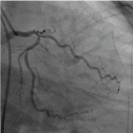

Presentation

Figure 2. Complete occlusion of right coronary artery

Figure 5. Right coronary artery after stent (AP view)

Figure 6. Right coronary artery after stent (LAO view)

In coronary angiogram, the proximal part of right coronary artery was occluded and it was compatible with ECG findings. And distal part of left main stem was totally occluded too– chronic total occlusion. The interventional cardiologist decided to treat the culprit vessels - right coronary artery and it was done successfully during the primary PCI. He left totally occluded left main stem for further intervention. It is in accordance with NICE guideline [9] and “Culprit Lesion Only PCI versus Multivessel PCI in Cardiogenic Shock (CULPRIT-SHOCK) trial”. Regarding complete occlusion of distal left main stem, the interventional cardiologist plan for staged revascularization. The patient was symptom free after the primary PCI and the blood pressure became normal. His serum creatinine fell gradually too. It was compatible with the findings of [5] where they found a significant reduction in all-cause death or renal-replacement therapy at 30-day follow-up in patients who had culprit-lesion-only PCI.